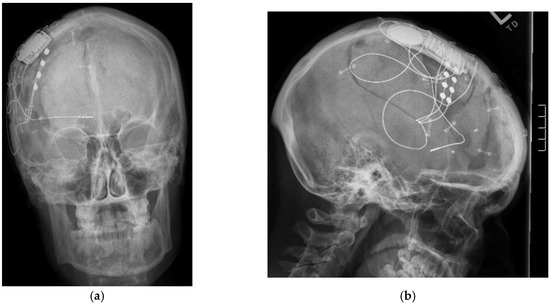

Figure 3.

(a) Antero-posterior skull X-rays of implanted responsive neurostimulation; (b) Lateral skull X-rays of implanted responsive neurostimulation.